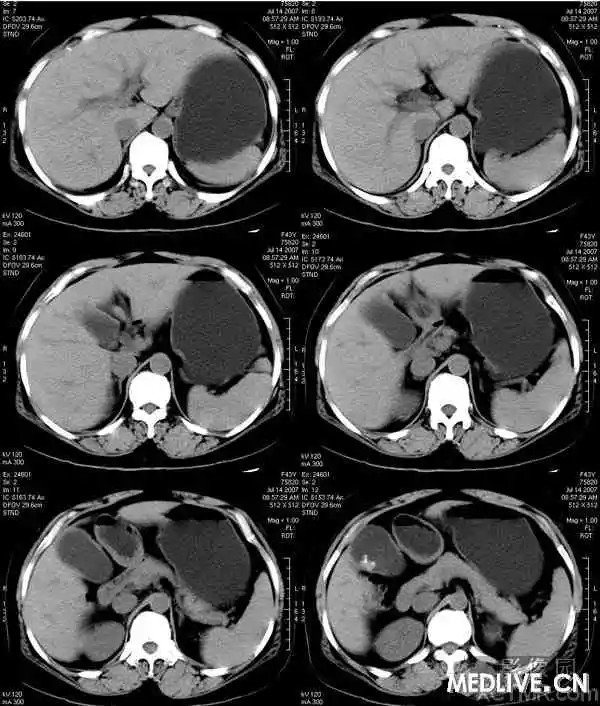

【影像表现】

胆囊内混杂高密度影,内有不规则形钙化,胆囊壁略增厚。